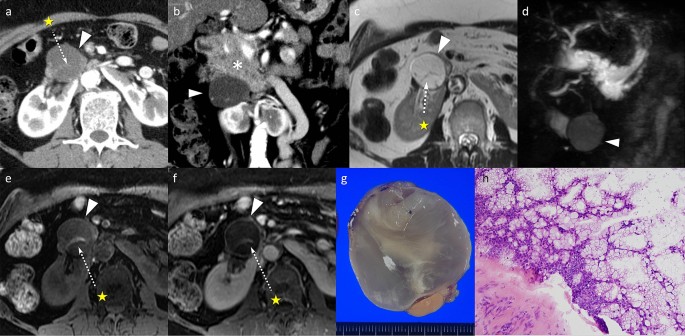

A Case Of A Solid Renal Mass Together With A Cystic Pancreatic Lesion In A 50 Year Old Patient Insight Medical Publishing

Lactoferrin Amyloid Presenting As A Mural Nodule In A Pancreatic Cystic Lesion Prompting Pancreatoduodenectomy A Case Report Bmc Gastroenterology Full Text